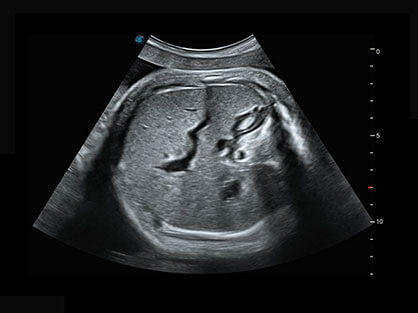

自动获取标准切面,自动完成测量,帮助医生快速完成检查,同时提升测量准确性。

宽频带腹部凸阵探头和腹部容积探头、大角度腔内探头和腔内容积探头、独特的生殖专用曲柄探头,为妇产应用提供全面诊疗方案。